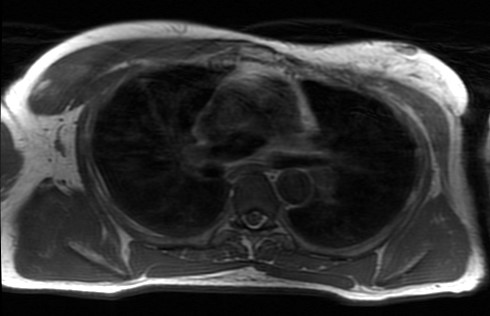

π It's time for Case #108 BIDMC Musculoskeletal Imaging & Intervention! β What is the name of this sign and what 3 components must be present? π Let us know by next Friday, Dec. 2! #Radiology #MSKRad #MedTwitter #CaseOfTheWeek Jim Wu SwatiDeshmukh,MD